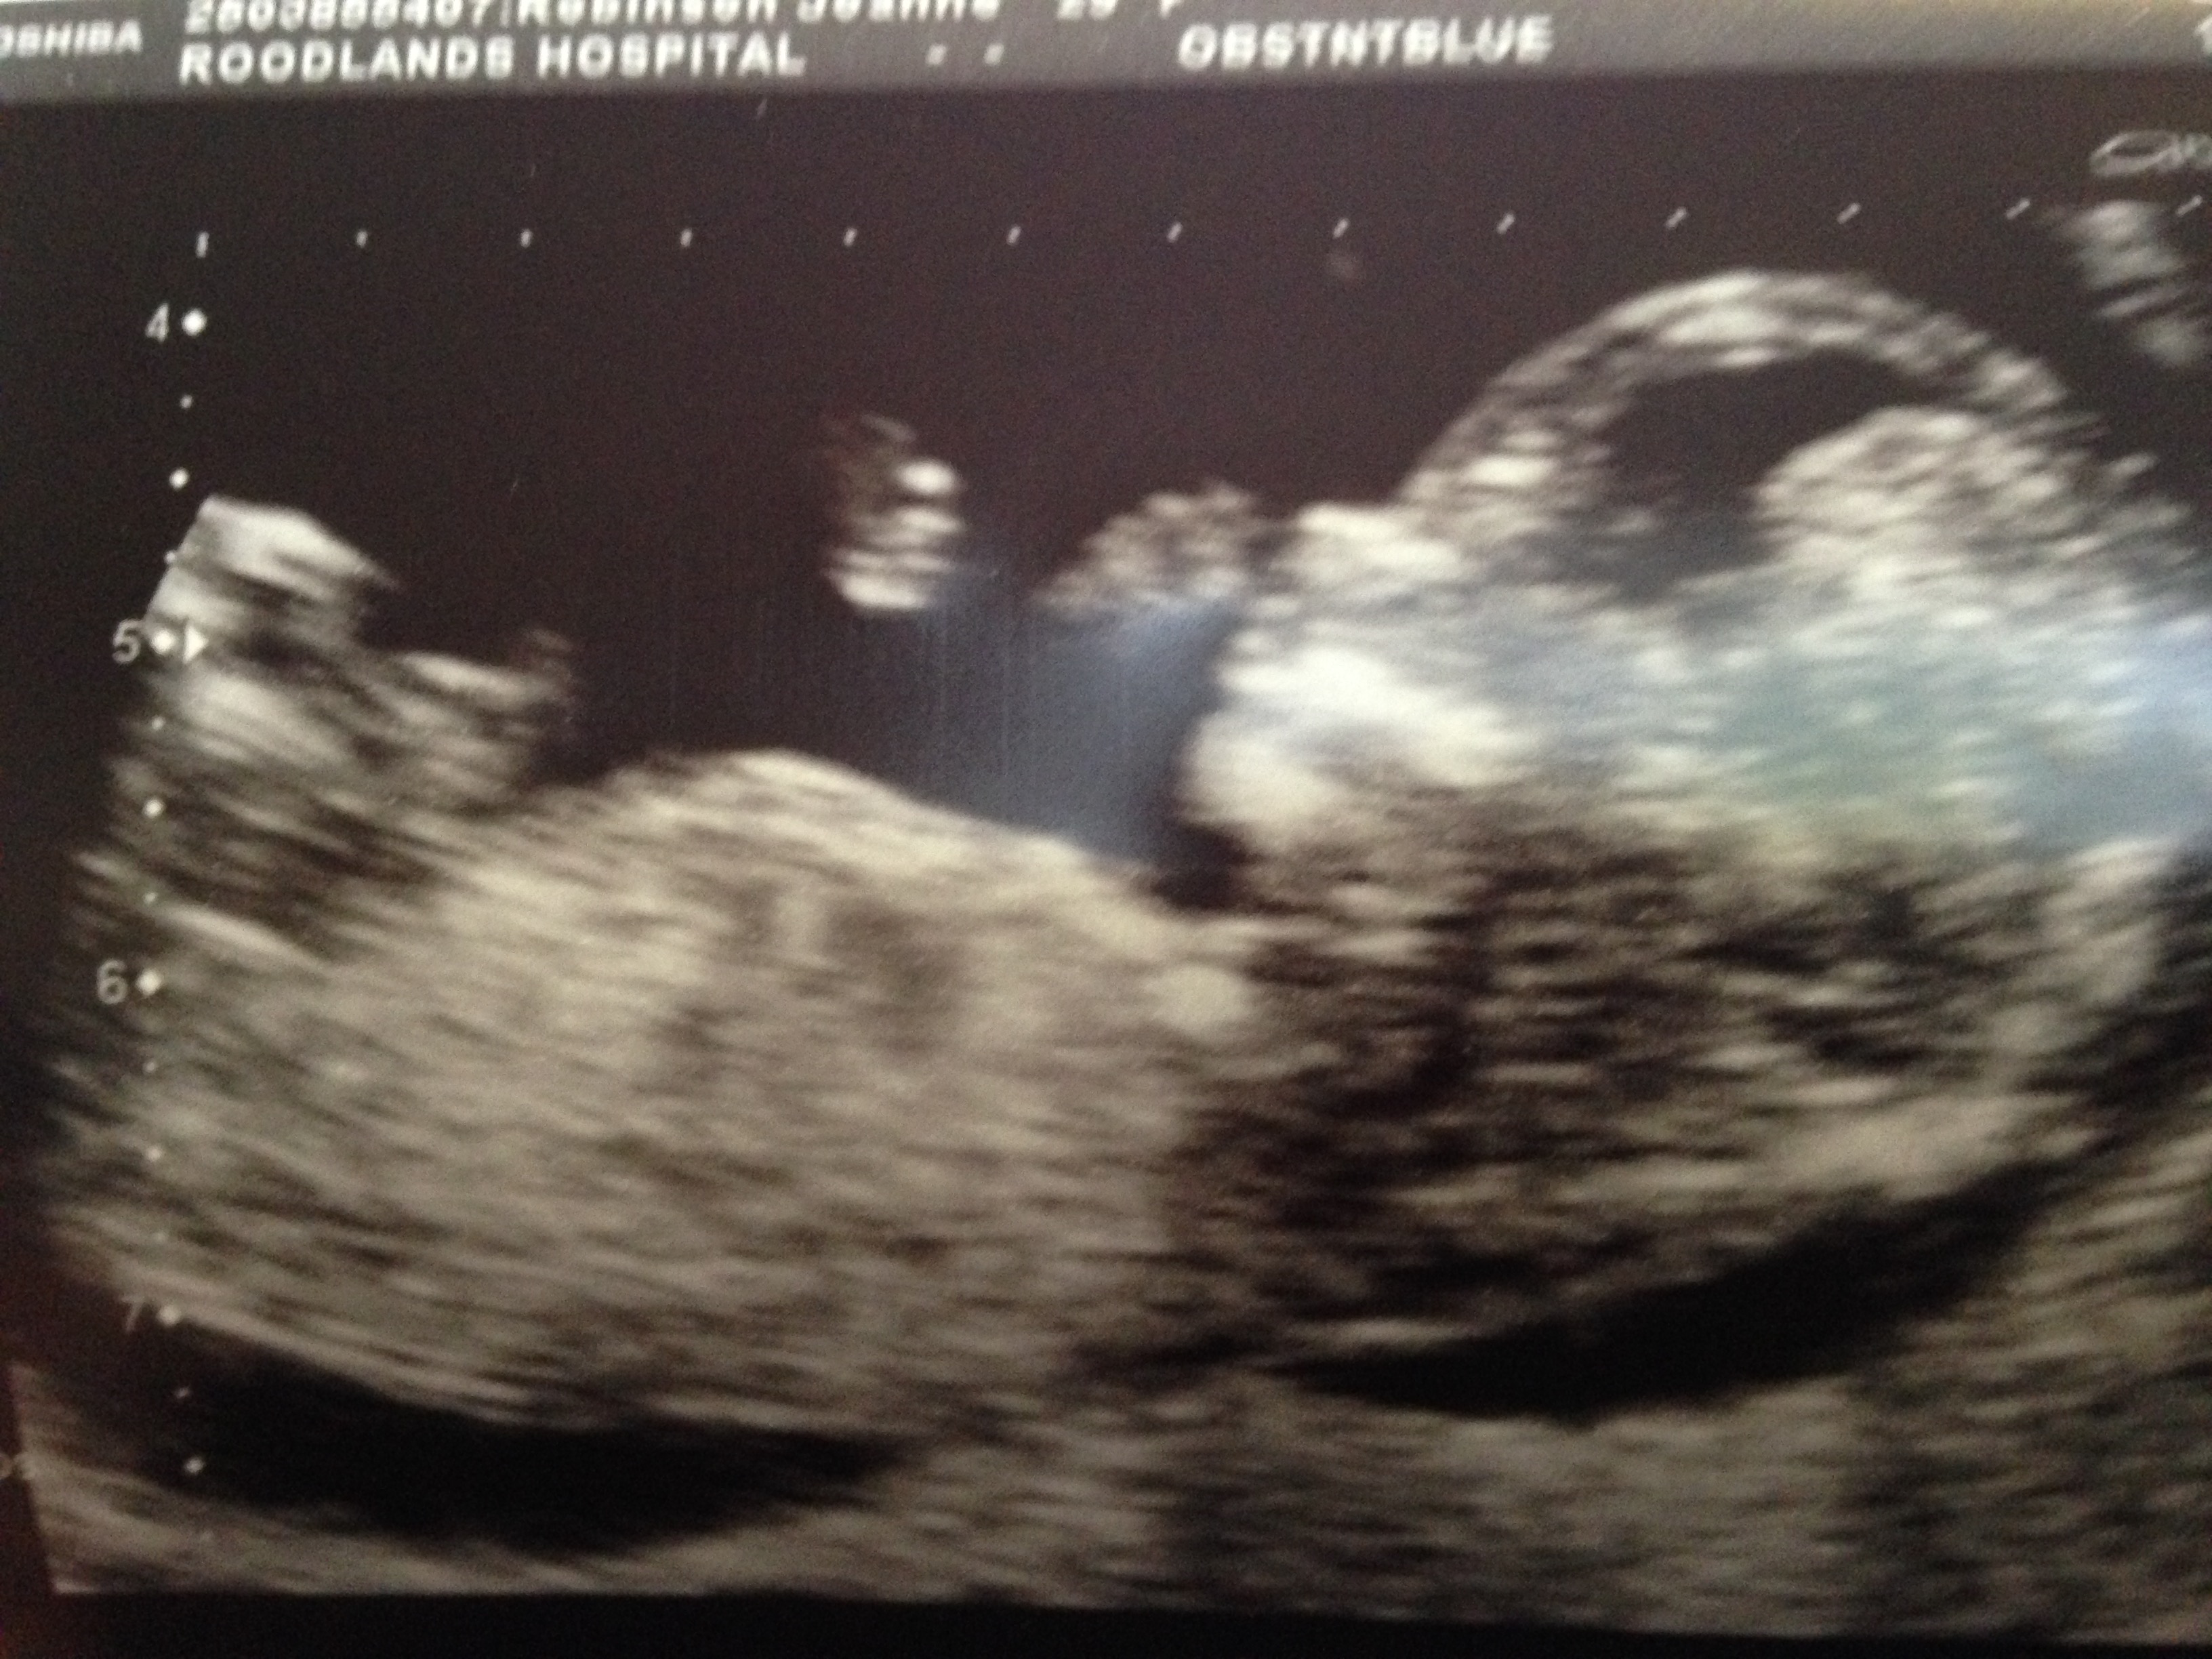

pretty please nub gusses its driving me crazy 12w 6 days

Attachment 21866

All guesses welcome.